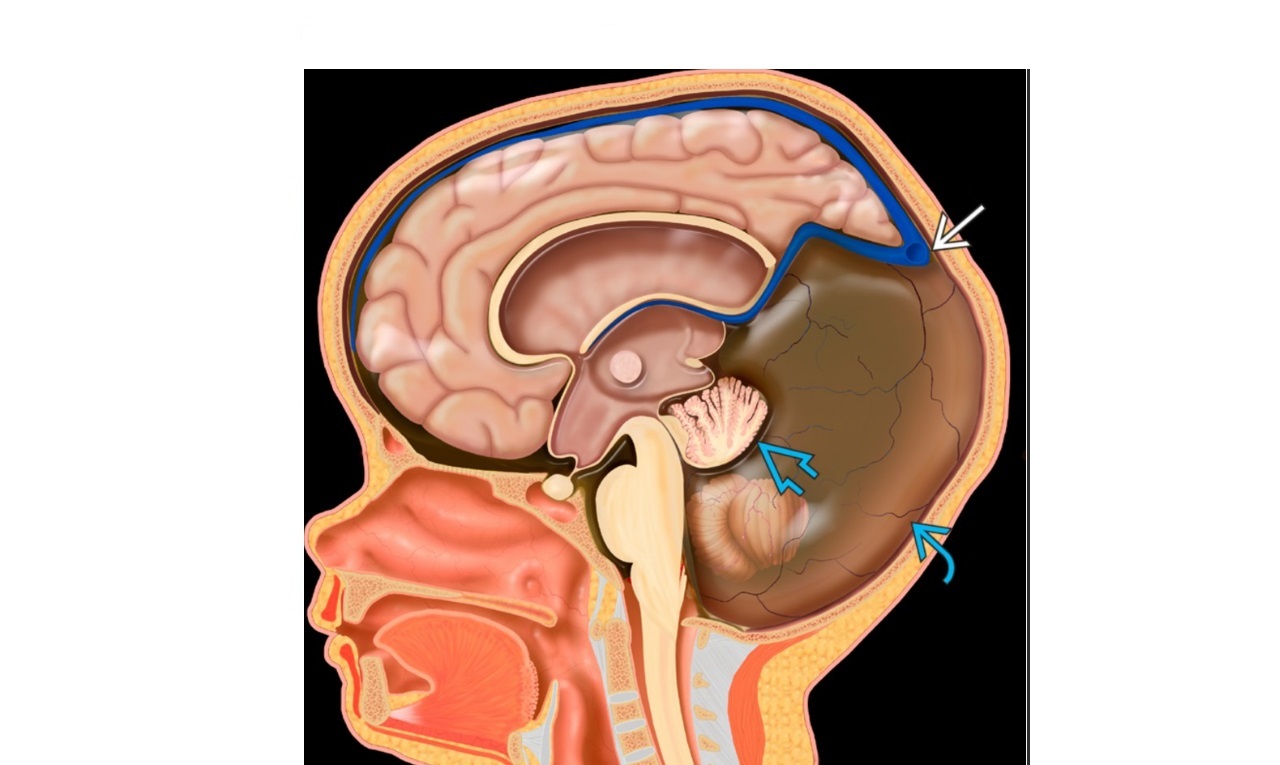

Features of Chiari 2 malformation?

= **Small posterior fossa with cerebellar compression and hindbrain herniation through foramen magnum ** -cerebellar herniation -4th ventricle compression = hydrocephalus -obliteration of the cisterna magna ***-lumbar myelomengiocele*** Other findings include ***callosal dysgenesis*** tectal beaking enlarged massa intermedia cervical medullary spUR Foetal US -Banana sign if cerebellum wraps around midbrain -Frontal bone concavity (lemon sign) CT and MRI -colpocephaly (enlarged occipital horn and atria) ‘batwing’ configuration of frontal horns on coronal view (pointing inferiorly secondary to enlarged caudate nucleus), -‘hourglass ventricle’ - excessive cortical gyration (stenogyria)